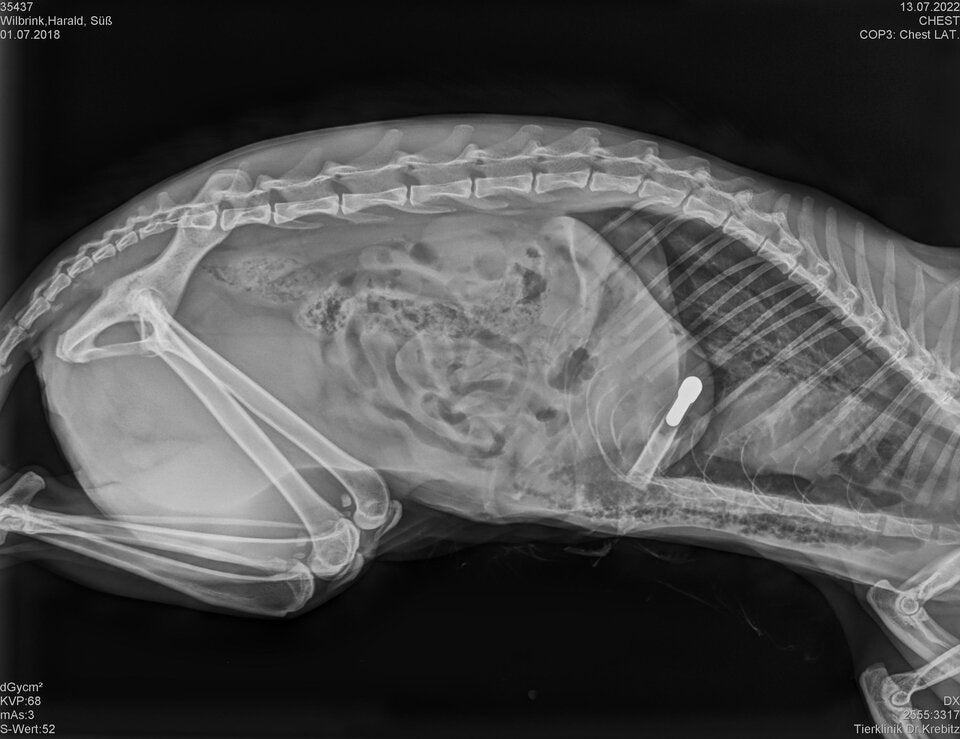

Kärnten. Mittwochnachmittag schoss ein bisher unbekannter Täter im Bereich Zmuln, Gemeinde Liebenfels (Bezirk St. Veit an der Glan) mit einem Pfeil auf eine freilaufende Katze. Der Pfeil durchbohrte die Katze, verletzte diese im Bereich der Lunge und blieb in ihr stecken. Die Katze wurde in eine Tierklinik in Klagenfurt gebracht und der ca. 80 cm lange Pfeil operativ entfernt. Das Tier befindet sich derzeit in äußerst kritischem Zustand.

© LPD Kärnten